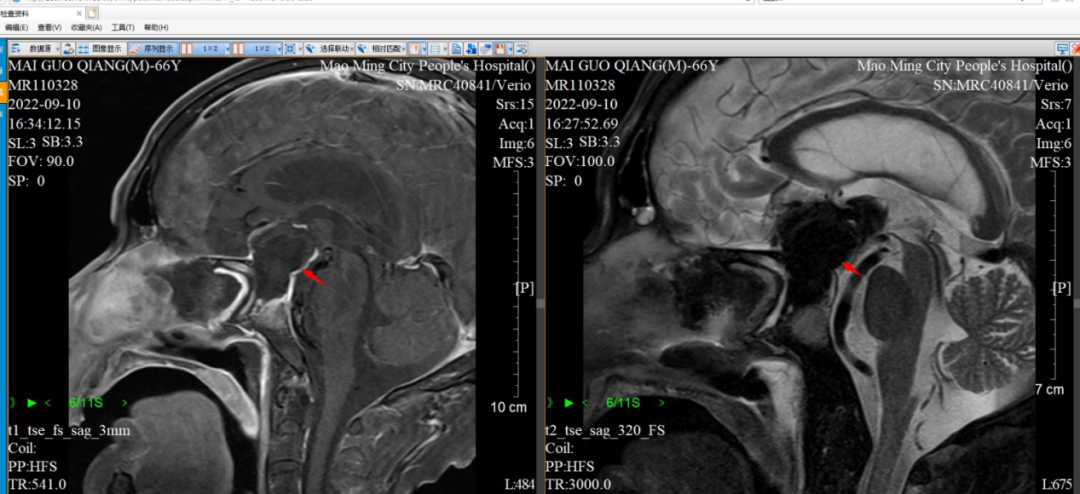

手术如期进行,经过接近5个小时焦心的等待,随着手术室门口护士的招呼,麦先生的家属怀着忐忑的心情急切上前,传来的是让家属心头落地的消息:手术由周向阳博士、赖廷海主任医师、何春柳医师集体完成,手术相当成功,麦先生颅内的肿瘤被完全切除,并且脑积水的通路也已经打通,脑积水同时也可能逐步缓解。

▲患者术后MRI提示肿瘤消失